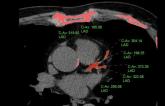

Diagnosis of SCAD on CTA & MRI

Presentation SCAD 2018

Presenter: John R. Mayo

September 08, 2018